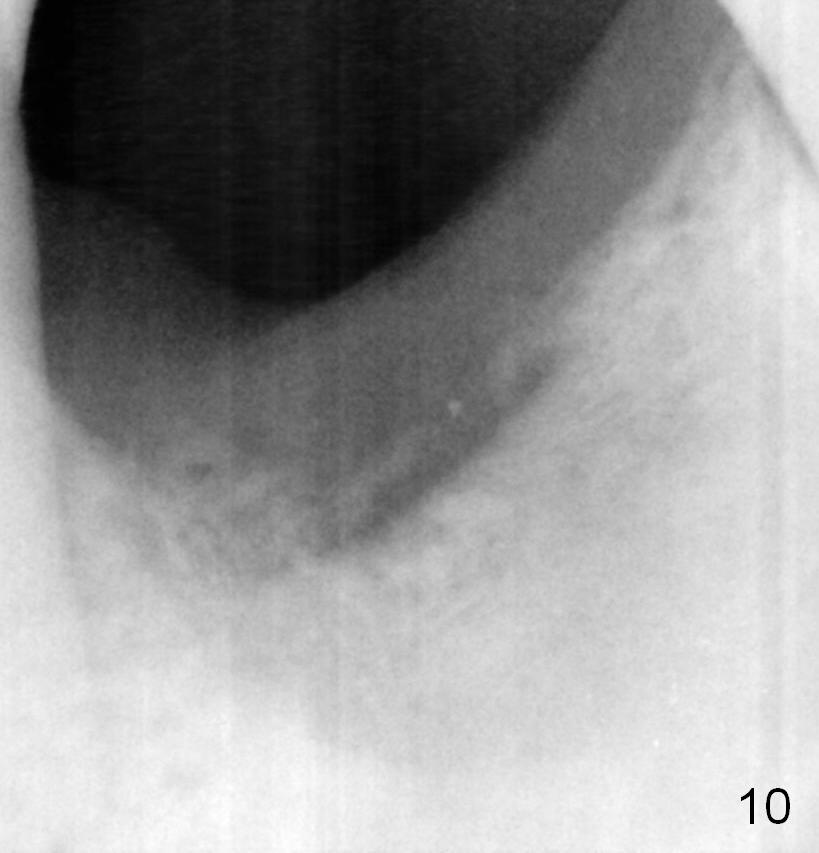

There is bone growth in the mesial socket 5 months post graft (Fig.10).